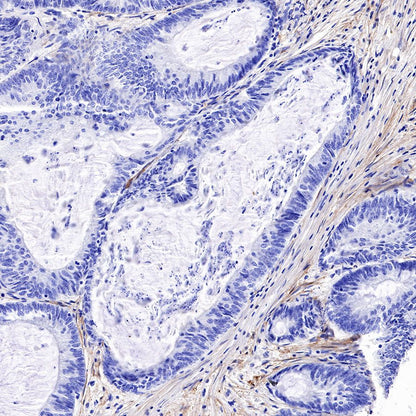

Immunohistochemistry

Negative control: IHC shows negative staining in paraffin-embedded human liver. Anti-FAP antibody was used at 1/500 dilution, followed by a HRP Polymer for Mouse & Rabbit IgG (ready to use). Counterstained with hematoxylin. Heat mediated antigen retrieval with Tris/EDTA buffer pH9.0 was performed before commencing with IHC staining protocol.